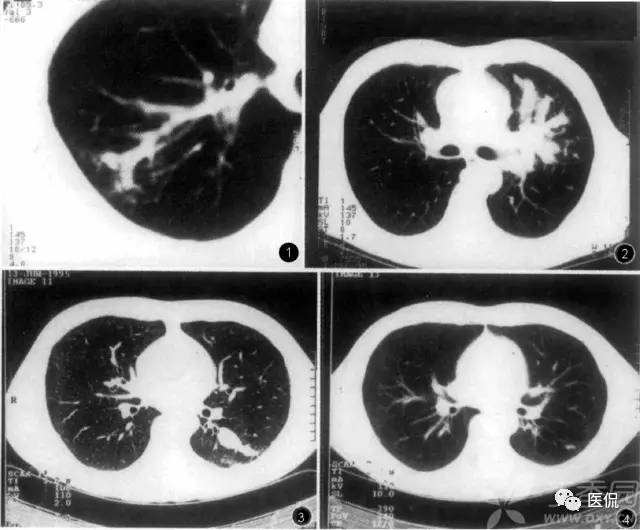

星系征

肺结节病的大结节(直径大于1公分)有无数小结节构成,大结节周围环绕小结节卫星灶,晚期支气管血管周围受累呈条带状,这与天文领域的卫星、慧星、银河很相象,这些影像表现与肺结节病的病理学表现很相似。“星系征”就是用来描述这一影像学表现的一个征象。需要注意的是,具有星系征这一征象的并不仅仅只有肺结节病,有时候,其他疾病如肺结核、肺转移瘤、细支气管肺泡癌及癌性淋巴管炎等也会出现这种征象。

1、小星星状:结节病肺内结节多发于胸膜下、叶间裂旁及沿支气管血管束周围分布,多表现为边缘模糊、不规则的网织结节或小叶中心结节,结节大小2~5 mm ,弥漫在双肺内似聚集在一起的成簇的小星星,此征象应与肺内转移瘤鉴别,转移瘤多发生于双下肺,边缘较光滑,多发孤立结节。

2、卫星状 : Ⅲ期的为肺内弥漫的小结节,大小约1 mm ,融合成大结节后通常可达到1~2 cm 左右,最大为2~4 cm ,边缘不规则,周围可见小的结节卫星灶环绕大结节周围,呈卫星状,中间的大结节酷似太阳,四周酷似它的卫星。

3、慧星状 :肺实质融合的大结节周围可见肺泡性渗出,呈毛玻璃状,好象长长的尾巴。

4、银河状 : Ⅳ期的结节患者,支气管血管周围同时受累,沿支气管血管束周围分布,支气管血管壁呈结节状增厚〔3〕,其间可见含气或扩张的支气管,呈条带状,与正常肺组织之间有清楚的分界上述表现的病理基础是病理变化为主炎性病灶表现:非干酪样肉芽肿和淋巴细胞肺泡炎,主要由上皮细胞组成的肉芽肿结节,体积小,结节内无干酪样坏死,常有多核巨细胞以及散在淋巴细胞,周围较多的淋巴浸润,以后为纤维包绕,结节融合。

肺结核星系征:

肺结节病星系征: